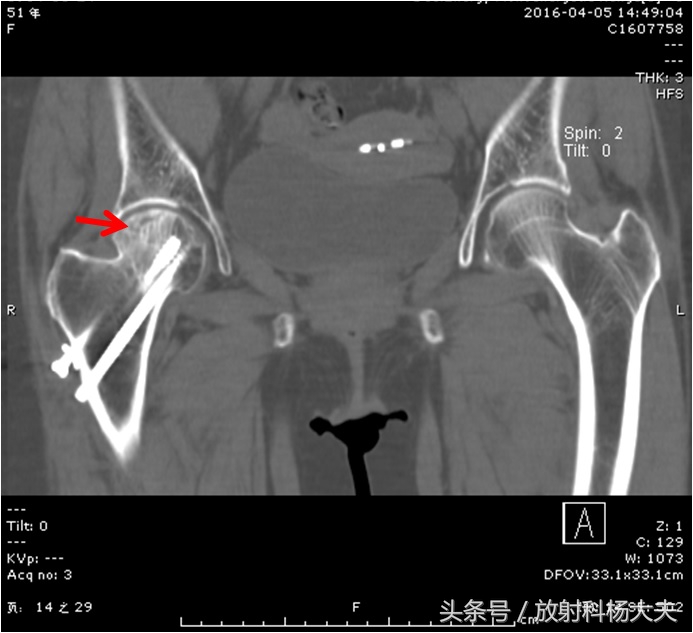

后来又复查的时候做了CT,CT上这个坏死也很明显。

红箭为右侧股骨头坏死。可见植入体内的金属钉